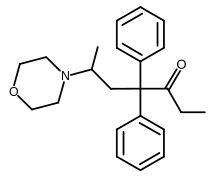

The first fully synthetic opioid was meperidine (later demerol), found serendipitously by German chemist Otto Eisleb (or Eislib) at IG Farben in 1932.[228] Meperidine was the first opiate to have a structure unrelated to morphine, but with opiate-like properties.[199] Its analgesic effects were discovered by Otto Schaumann in 1939.[228] Gustav Ehrhart and Max Bockmühl, also at IG Farben, built on the work of Eisleb and Schaumann. They developed "Hoechst 10820" (later methadone) around 1937.[230] In 1959 the Belgian physician Paul Janssen developed fentanyl, a synthetic drug with 30 to 50 times the potency of heroin.[211][231] Nearly 150 synthetic opioids are now known.[228]